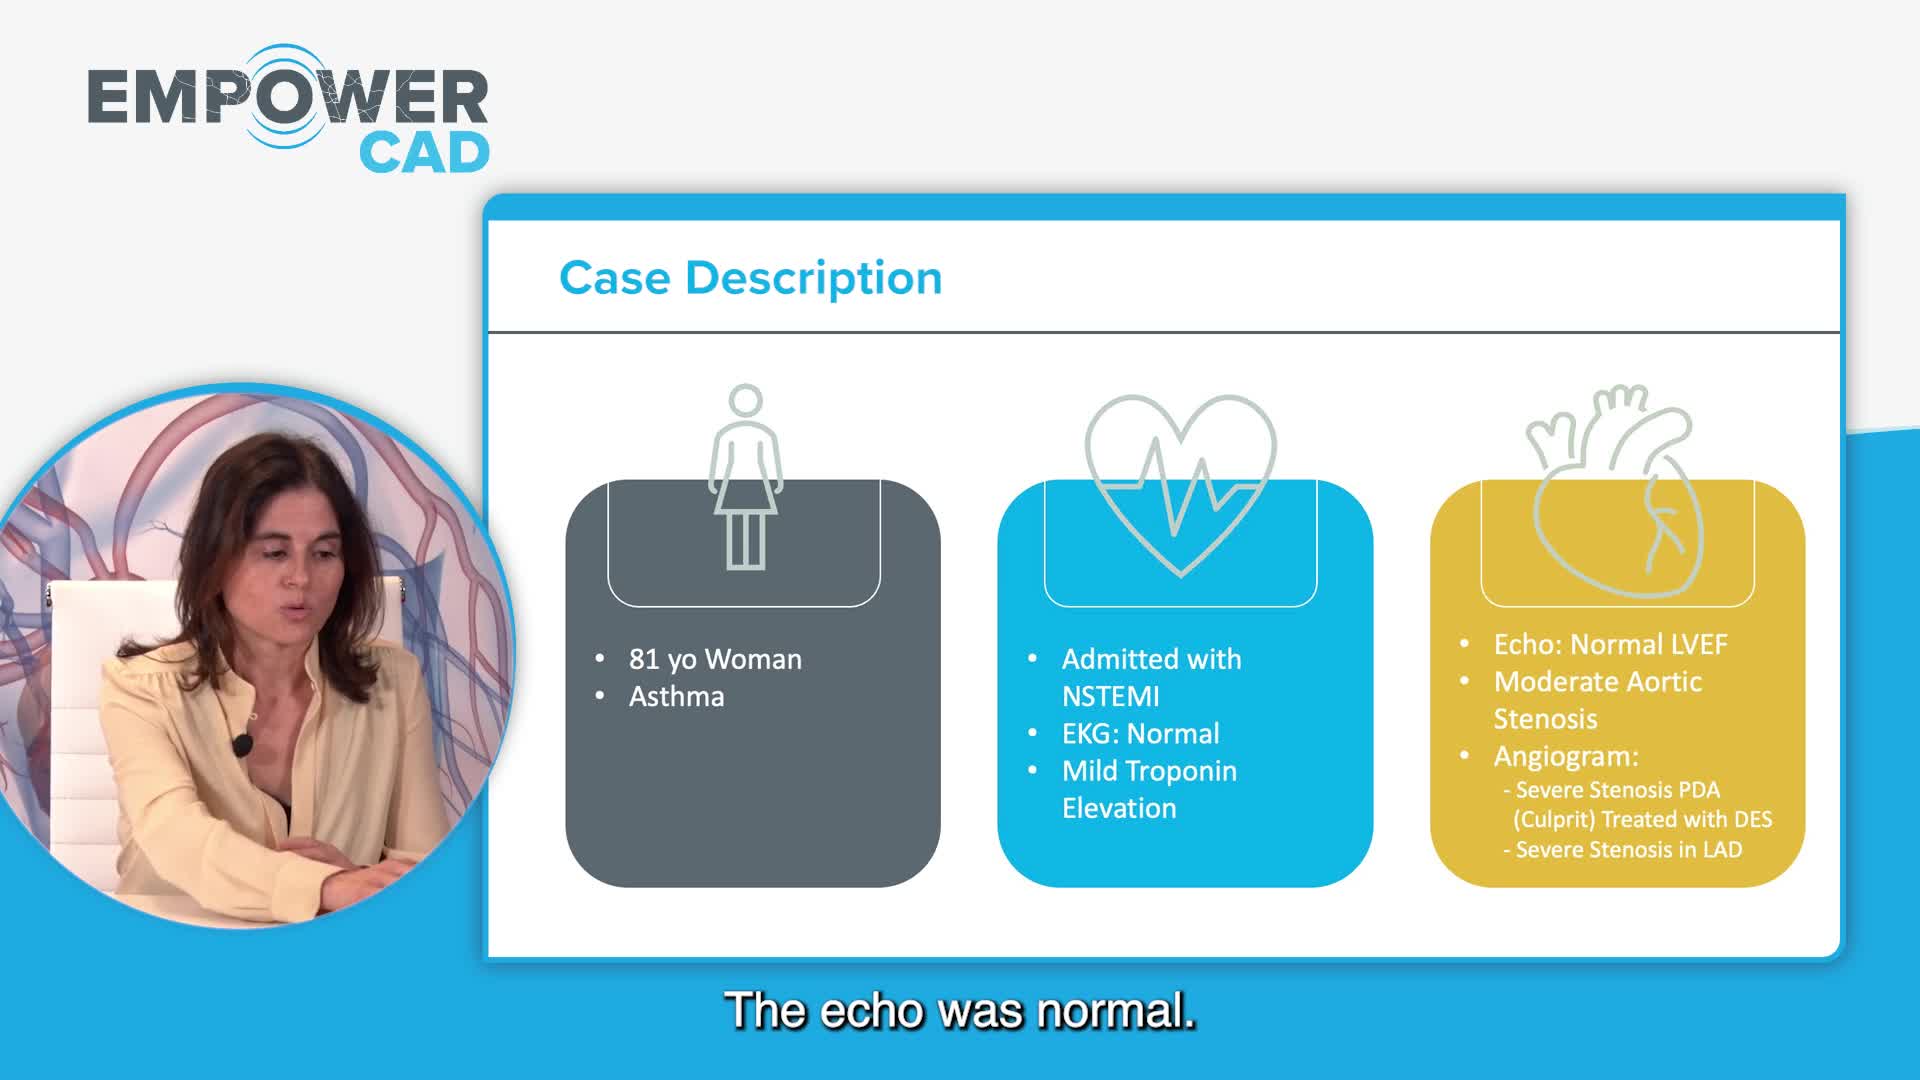

Coronary IVL Greatest Hits

Real-World EU Experience: Coronary IVL Across Different Calcium Morphologies from TCT 2022

Shockwave IVL Coronary Real-World Cases, Outcomes & Algorithms: An InCathLab Webinar